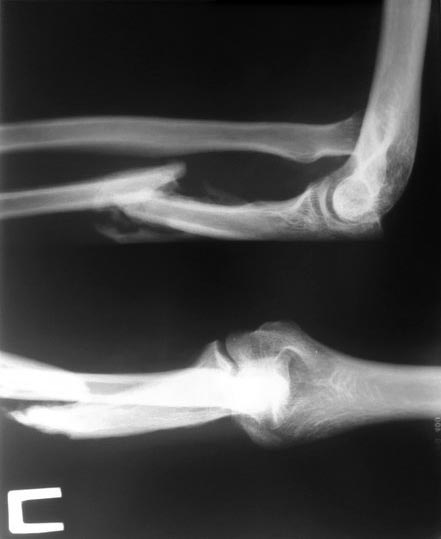

Пациентка из неблагополучной семьи получила травму в мае 2015 года , в

следствии удара тупым предметом в область в/3 предплечья, за мед помощью

не обращалась. К нам обратилась через 4 месяца. По данным Ro -

застарелый вывих головки лучевой кости з неверно консоледирующимся

переломом в/з локтевой кости. Ваша тактика лечения. Прилагаю снимки.

Добавлю, что клинически функция локтевого сустава нарушена, сгибание 30

-40 градусов, предплечье деформировано, болезненно при пальпации в

проксимальном отделе .